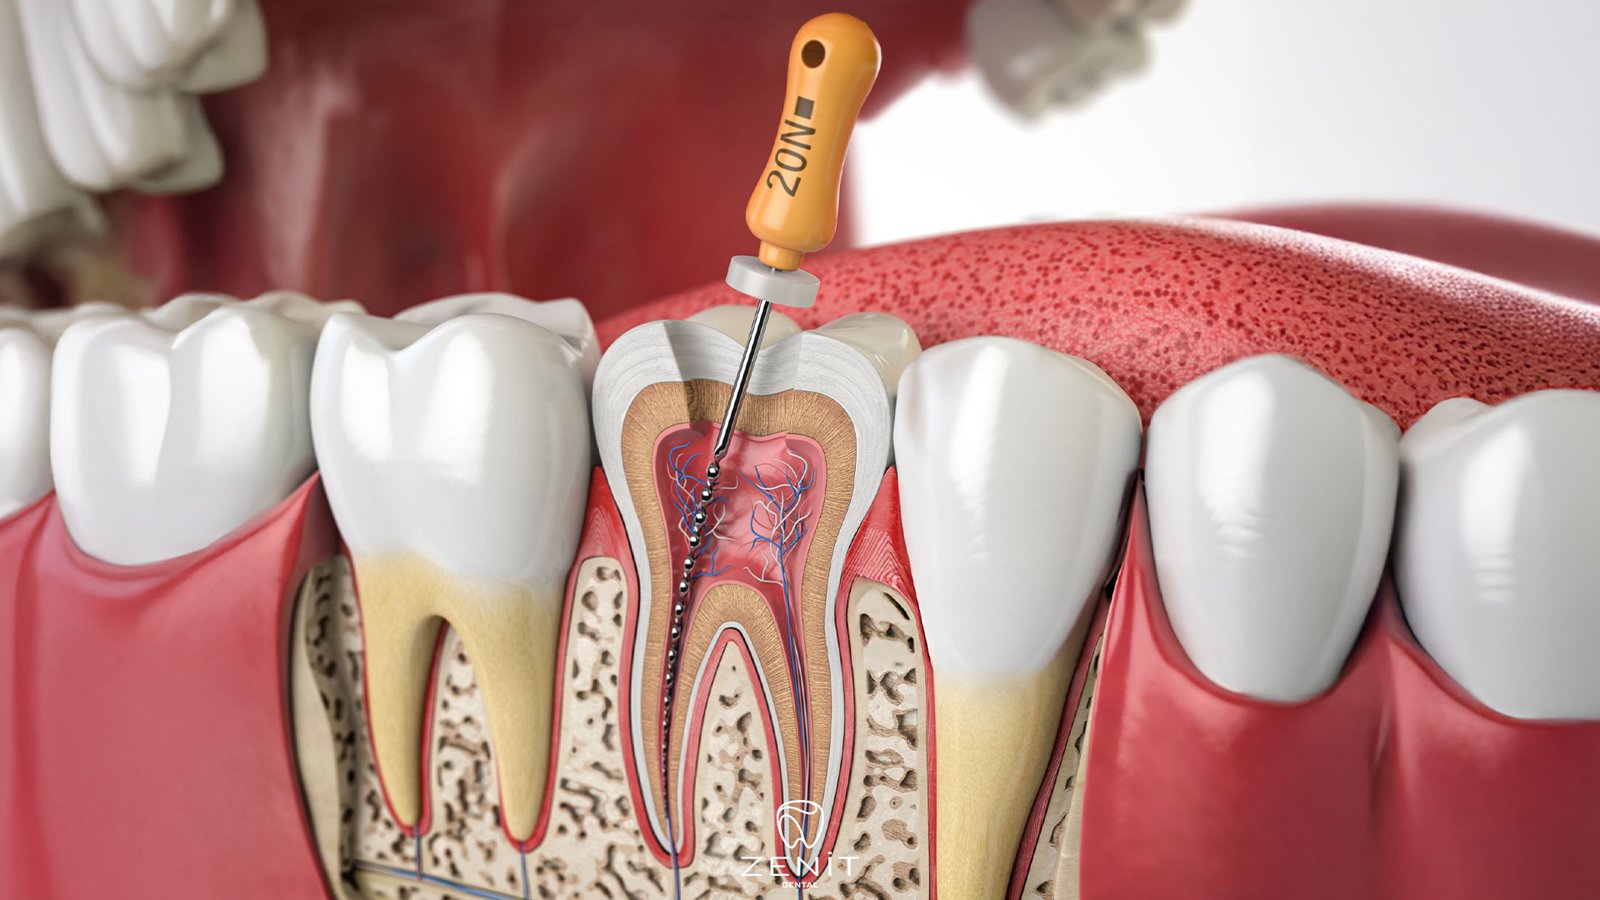

Retreatment, yani dişin yeniden tedavisi, aslında önceden yapılmış kanal tedavisinin bir “gözden geçirilmesi” gibi düşünülebilir. İşlem başladığında, diş hekimi ilk olarak eski dolgu veya tıkaç malzemeleri dikkatlice çıkarır. Bu adım, dişi yeniden temizleyip enfeksiyonu tamamen ortadan kaldırmaya hazırlamak için oldukça önemlidir. Eski dolgunun çıkarılması sırasında diş, tekrar şekillendirilmeye ve tedaviye hazır hale getirilir.

Sonrasında, dişin içindeki kanallar titizlikle temizlenir. Buradaki amaç, eski tedaviden kalan enfekte dokuların tamamen yok edilmesidir. Bazen enfeksiyon gözle görülmeyebilir ama dişin içinde sessizce ilerleyebilir. İşte bu yüzden kanalın derinlemesine temizlenmesi, retreatment’in en kritik aşamasıdır.

Temizlikten sonra kanallar yeniden şekillendirilir ve steril dolgu malzemesi ile doldurulur. Bu dolgu, dişi enfeksiyonlara karşı korur ve uzun süreli dayanıklılığını sağlar. Dolgunun ardından diş, tekrar eski formuna kavuşması ve çiğneme fonksiyonunu sağlıklı şekilde yerine getirebilmesi için üst dolgu veya kaplama ile tamamlanır.